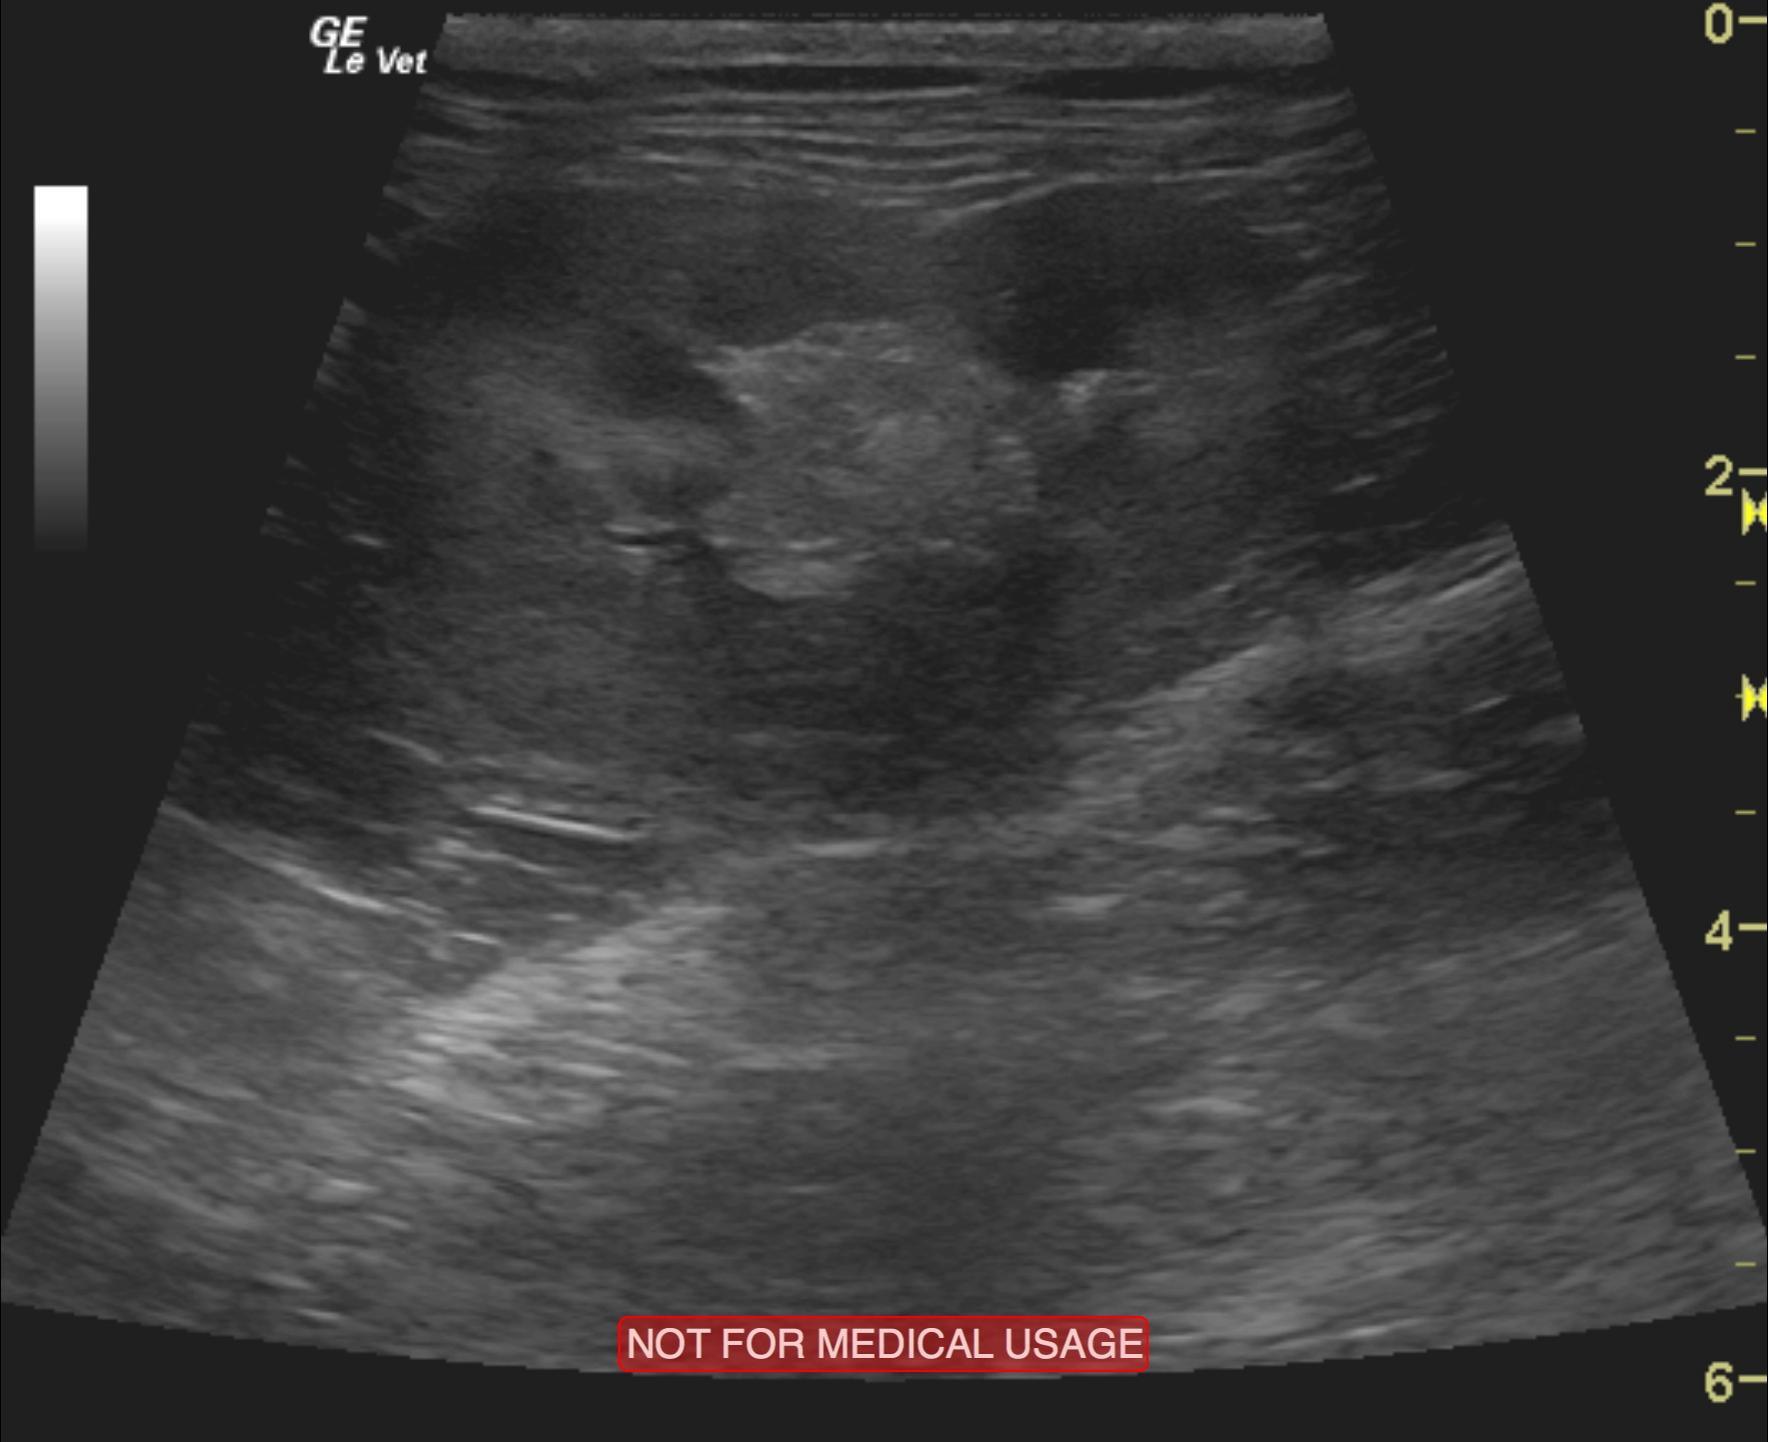

A 5-year-old male neutered DMH cat was presented for evaluation of PU/PD, abnormal behavior, and inappropriate urination (periuria). Low-normal specific gravity (1.014) was evident on urinalysis. CBC was within reference range, but serum biochemistry revealed azotemia.